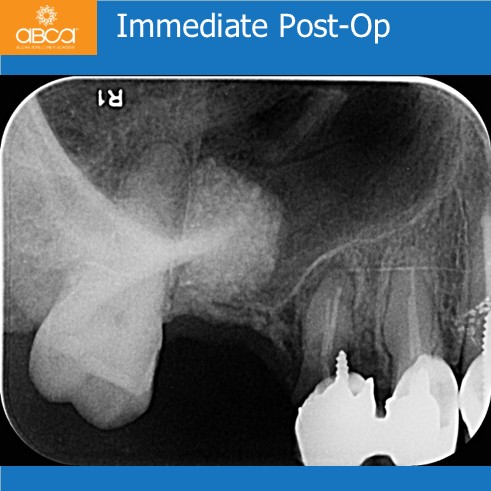

Initial CBCT images show the estimated ridge height as 1-2mm below the sinus. The BY2 diamond milling bur breaks through the sinus floor. Following the Augma Lift™ technique protocol, membrane elevation and augmentation are performed. Radiography shows implant placement 4 months post-op in newly formed bone.